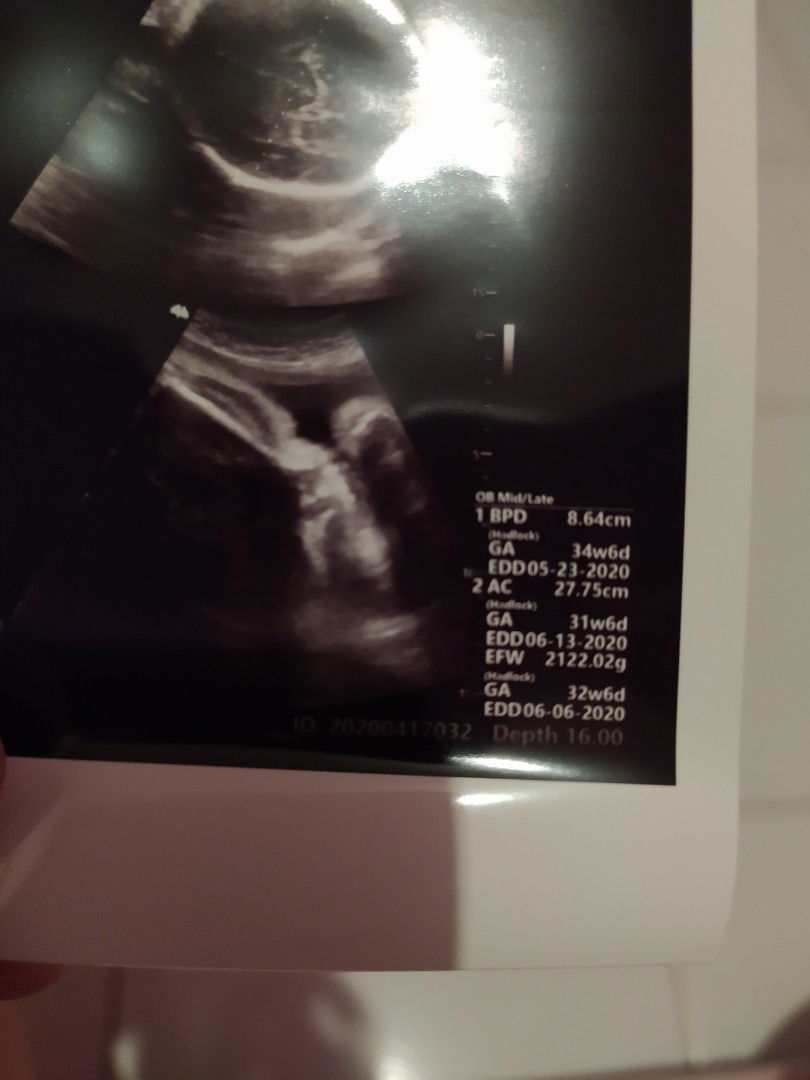

hasil usg

Bun ada yg tau cara baca hasil usg ini? 2minggu lalu saya kontrol hpl masih sama yaitu tgl 4 juni, tp td usg lg kok jadi 6 juni ya?